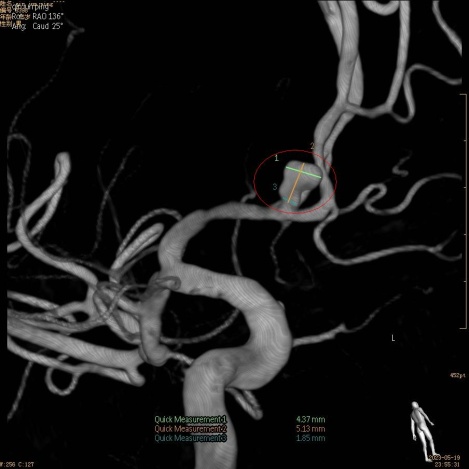

小覃第一次见东莞康华医院神经外科主任王咸昌,是个“不开心”的回忆,他被王主任告知——他的左侧大脑前动脉与前交通动脉交界处有个5.1mmx4.6mmx2.6mm动脉瘤,病情严重,用常规的治疗方式“拆除”,有可能造成严重的后遗症。

术前脑血管影像:

DSA主动脉弓造影可见患者血管扭曲,介入通路建立困难,增加了手术难度和风险。经桡动脉在绕行的同时还要把支架、弹簧圈顺利送到目标动脉瘤处释放,对医生来说是一个技术挑战。经过神经外科团队会诊、综合研判和评估风险后,缜密制作了脑血管造影、经桡动脉行颅内动脉瘤介入栓塞术等手术方案,争分夺秒为患者赢取更多生机。在麻醉科、放射科等科室协作下,手术如期进行。

“脑血管造影成功!”术中先是脑血管造影检查显示,再次精准定位并证实了患者的动脉瘤病变部分存在,是前交通动脉瘤破裂伴蛛网膜下腔出血。“弹簧圈栓塞成功!”紧接着,在王咸昌主任的指导下,神经外科彭先华医师 带领团队眼疾手快地精准操作手术,通过微导管把特制的栓塞材料“弹簧圈”完全填充整个动脉瘤,为患者拆除了这颗“不定时炸弹”,术后造影提示动脉瘤均完全栓塞,载瘤动脉通畅,全程手术历时2小时左右——宣告成功。